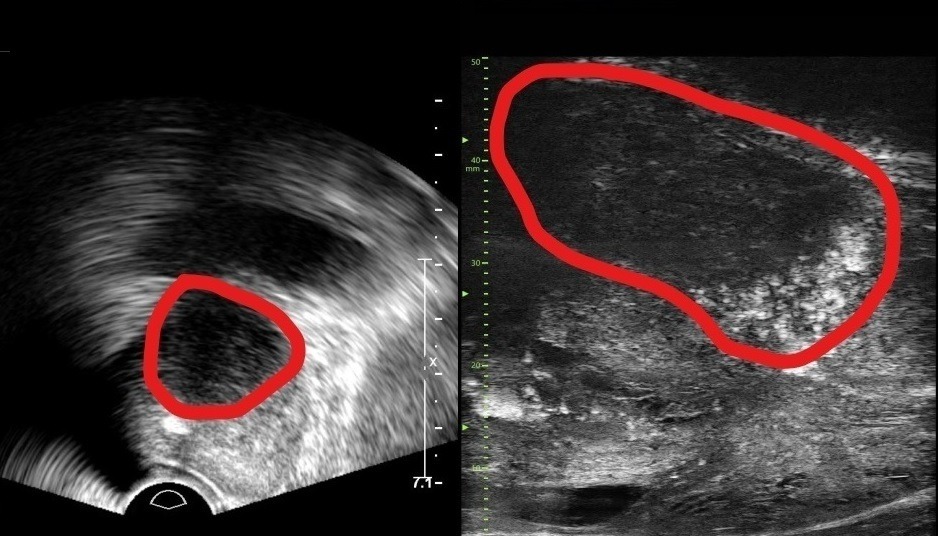

29MHz 마이크로 초음파를 사용하는 이 장비는 전립선과 주변의 해부학적 구조를 선명히 표시하고 표적 조직검사를 유도한다. 의심 영역을 실시간으로 확인하면서 전립선 조직의 미세한 변화와 병변을 식별하고 조직검사 채취를 위한 바늘을 정확한 위치에 삽입할 수 있다는 장점이 있다.

또한, 전립선 암 진단을 위한 초음파 검사 가이드인 PRI-MUS(Prostate Risk Identification Using Micro-Ultrasound) 위험도 식별 시스템과 연계돼있어 전립선암 병변의 악성 가능성 평가는 물론, 어느 부분에서 조직을 채취해야 하는지 정확히 판단할 수 있게 한다. PRI-MUS는 초음파 상 병변의 모양이나 크기를 자동으로 판단해 병변의 악성도를 1~5단계(높을수록 위험)로 분류하기 때문에 불필요한 조직검사를 줄이면서도 암을 놓치지 않게 돕는다.

기존의 경직장 초음파는 해상도가 낮아 전립선 종양, 특히 작은 암 병변을 감지하는 데 한계가 있었다. 하지만 마이크로 초음파의 높은 해상도와 실시간 영상의 시각화는 자기공명영상(MRI)으로 발견할 수 없는 전립선암을 찾을 때도 충분히 기여할 것으로 기대하고 있다. MRI 검사 보다 환자의 신체적, 심리적, 경제적 부담도 적을 수밖에 없다.